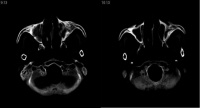

新生儿声门前后径为7mm,后端横径4mm。若前者小于5mm,后者小于3mm,视为先天性小喉。先天性小喉的内部结构正常,但因喉腔窄小,严重者常不能维持正常通气量。

直接喉镜检查可见喉部各结构皆较小,声门短而窄。颈部触诊甲状软骨亦较正常者为小。